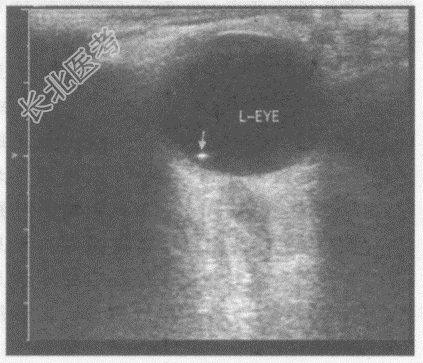

- 单项选择题女,33岁, 爆炸伤后左眼不适。超声综合描述:双眼球形态正常, 双眼球玻璃体内可见数个点状强回声(箭头所示),后伴彗星尾征。超声提示:

D、左眼球内异物